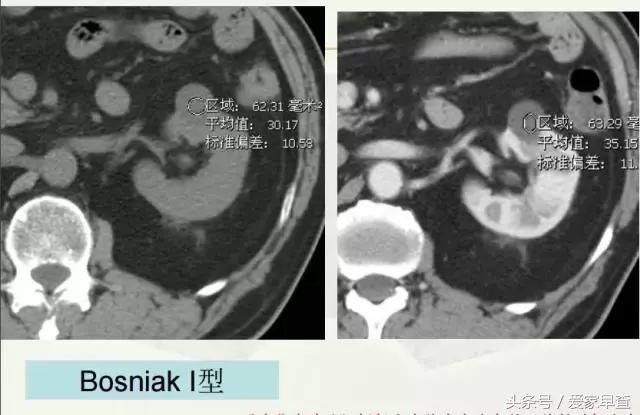

我们现在临床上采取的一个方法就是把各种各样的不同类型的囊肿,把它归成不同的分型。这个分型比较公认的一个分型叫Bosniak。 这个分型为什么被接受呢?是因为它跟临床的契合度非常好。比方说,如果我诊断是BosniakⅠ型,那就认为这是一个单纯囊肿,而单纯囊肿的恶性可能性几乎是零。如果是一个诊断为了BosniakⅣ型,可以认为它是囊性肾癌,看起来很好,但有一个前提,你要去做这个分型,必须要做增强扫描。

比方说这是Ⅰ型的,那么我们做了增强扫描以后发现没有血崩,边界很清楚,密度很均匀,又比较小,所以说这个就是Ⅰ型,单纯囊肿,只是个小水泡而已!对这种囊肿当它又不是很大的时候,就不需要管他,不需要处理。